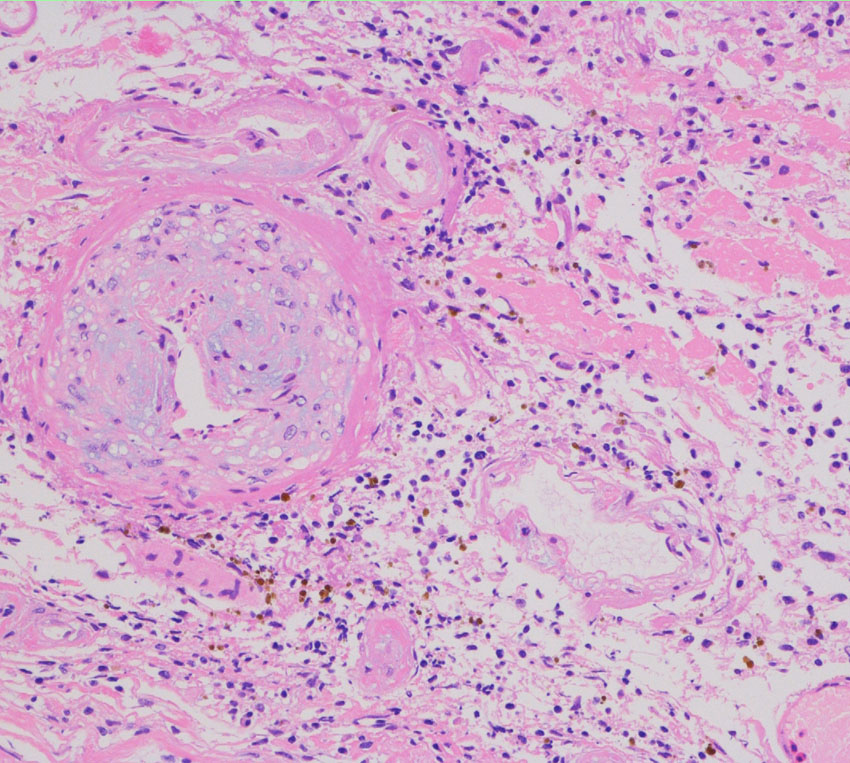

左側頭葉への腎癌の単発転移です。症候性てんかん(失語症発作)で発見され,定位放射線治療を受けたのですが,数ヶ月後に脳浮腫が高度となり失語症が悪化しました。コアになっている円形の転移腫瘍の周囲に放射線による脳壊死を疑いました。2時間ほどの開頭手術で,右側のガドリニウム増強されているところだけを摘出しました。

腫瘍中心の壊死の部分です。腫瘍細胞が死滅して凝固壊死の像です。血管はヒアリン化して閉塞しています。

腫瘍の辺縁部で手術中に血管が発達して出血があった部分です。腫瘍細胞 clear cell carcinoma が新生血管周囲に増殖しています。真ん中はPAS染色,右側はMIB-1染色で13%くらいの高い陽性率です。これは定位放射線治療で腫瘍が全部死滅していなくて一部では再発していることを示します。

さらに周辺と正常脳との境界部位です。脳組織が壊死になっていてます。放射線脳壊死が周囲にあって,高度の脳浮腫を生じていたことがわかりました。

この例は,定位放射線治療後に,1) ガン組織が壊死になって放射線治療の効果が認められる,2) ガン転移の再発がある,3) 放射線脳壊死が起こっている,という3つの事象が混じって生じているものです。ですから,PETやMRSなどで手術の前の画像診断を頑張ってみても,診断がつくはずがないのです。病理診断しか手段がありません。

手術1年半後の画像です。症状はなくて元気にお暮らしでした。新たな脳転移はありません。

この患者さんは幸運な方といえます。ガンを見る内科の先生に知っていただきたいのですが,今でも脳神経外科の手術は転移性脳腫瘍の治療に役に立つことがあります。